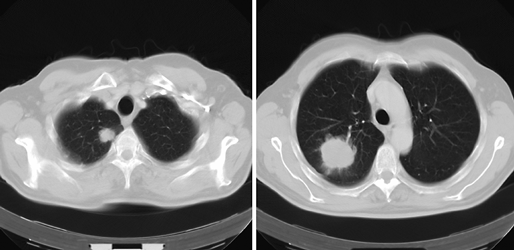

Первичной локализацией новообразования может быть, прежде всего, рак легкого (рис. 1), затем РМЖ, желудка и поджелудочной железы.

Рисунок 1. Периферический рак с метастазами в ткани той же доли